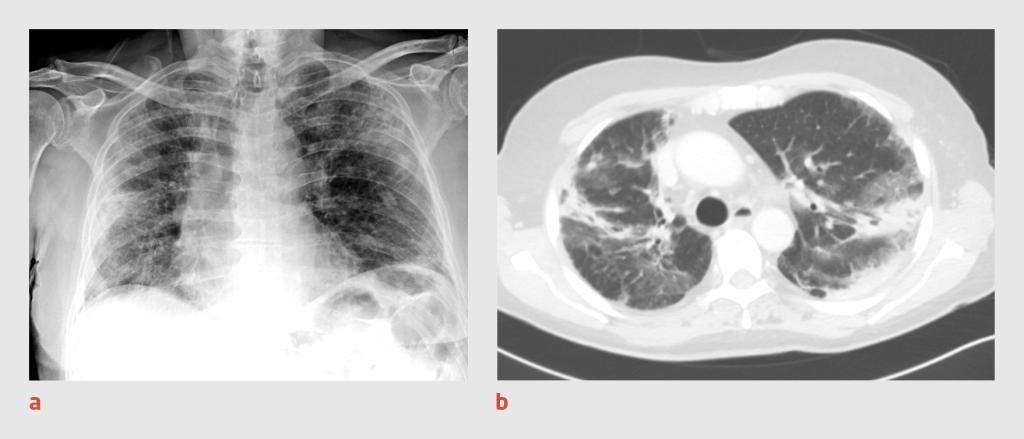

Figuur 1

Thoraxfoto en CT-thorax van patiënt A

Figuur 1 | Thoraxfoto en CT-thorax van patiënt A

(a) Thoraxfoto van een 30-jarige man waarop een ‘moppig’ beeld te zien is met diffuus verspreide consolidaties in beide longen, passend bij een atypische pneumonie. (b) Op de CT-scan van de thorax zijn in beide longen diffuus verspreide matglasafwijkingen en consolidaties zichtbaar, overeenkomstig een CO-RADS-score van 5.

Er wordt een PCR-test verricht op SARS-CoV-2 in materiaal uit de nasofarynx en patiënt wordt intraveneus behandeld met ceftriaxon 2 g 1 dd. De volgende dag blijkt de uitslag van de PCR-test negatief te zijn. Omdat wij nog steeds een sterk vermoeden van covid-19 hebben, wordt opnieuw een PCR-test verricht. Ook wordt er een CT-scan van de thorax gemaakt, waarop in beide longen diffuus verspreide matglasafwijkingen en consolidaties worden gezien (CO-RADS-score 5) (figuur 1b). Patiënt blijft zuurstofbehoeftig en wordt behandeld met chloroquine.